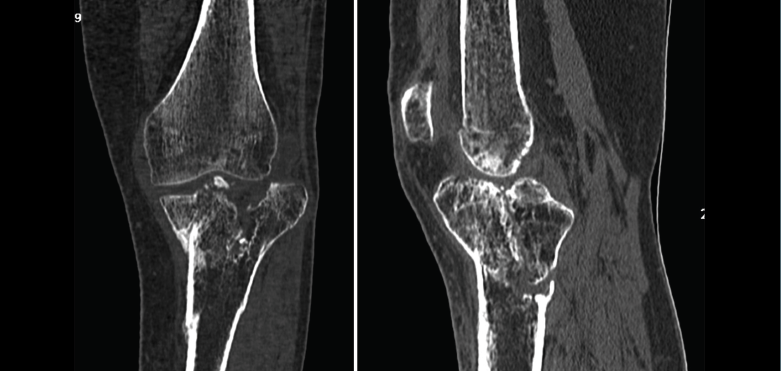

1.2. Tibia (Figura 20)

Figura 20. Corte de reconstrucción coronal de tomografía axial computarizada de rodilla: fractura de ambas mesetas tibiales.

La pseudoartrosis se define cuando, transcurridos al menos 6 meses desde la fractura, no se produce su consolidación y se evidencian muy pocos o ninguno de los signos de evolución radiográfica (Figura 22).

Figura 22. Corte de reconstrucción coronal y sagital de tomografía axial computarizada de rodilla: fractura metafisoepifisaria tibial sin consolidación después de 6 meses.